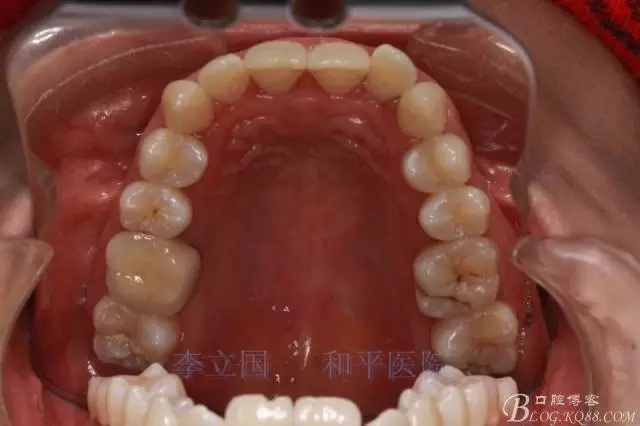

患者主訴前突。

1.患者上前牙直立,面型前突,典型的嘴凸牙不吐,關(guān)鍵是前牙轉(zhuǎn)矩控制,建議使用高轉(zhuǎn)矩托槽。

2.磨牙關(guān)系一側(cè)完全遠(yuǎn)中,一側(cè)遠(yuǎn)中尖対尖,采用兩個(gè)上4,一個(gè)下1的拔牙模式。